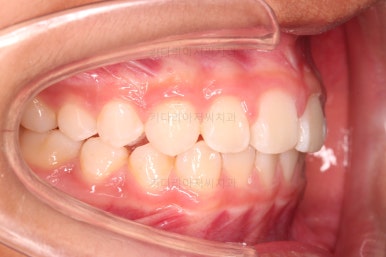

부산소아교정 마무리 사진입니다.

프리올소로 유지과정까지 총 2년 3개월 가량 걸렸고요.

전후 비교해 볼게요.

옆모습을 보면 턱끝의 윤곽도 살아났고요.

옆에서 웃는 모습을 보면 윗니도 들어간 모습이 보이죠.

물론 아직 약간의 돌출감이 있긴하지만 아이 기준으로는 나쁘지 않고, 특유의 두툼한 입술을 가진 환자분이라면 무조건 입이 많이 들어간다고 답은 아닙니다.

정교한 조절은 안했지만 치열이나 교합/맞물림 등 매우 좋아졌습니다.